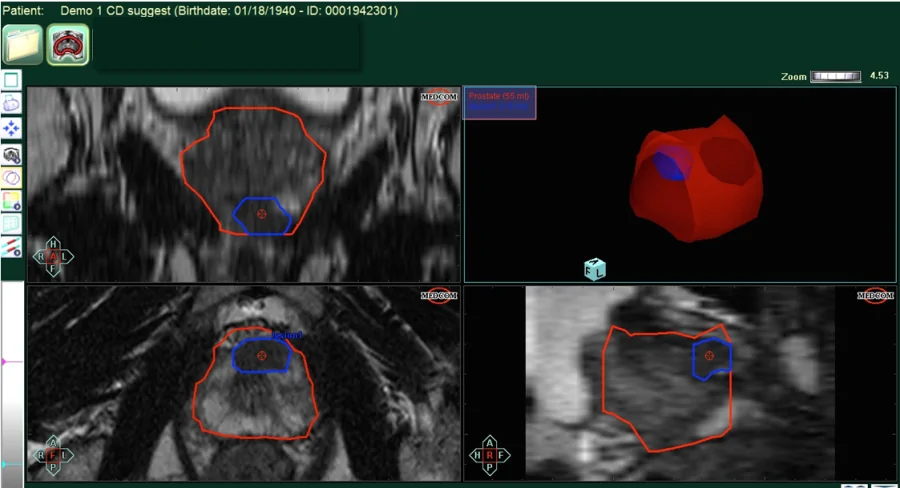

Κατά την πολυπαραμετρική μαγνητική τομογραφία προστάτη γίνεται πλήρης χαρτογράφηση του προστάτη σε όλη την έκταση του από την βάση προς την κορυφη (στην συγκεκριμένη εικόνα ο προστάτης έχει σχεδιαστεί με κόκκινο πλαίσιο), και παράλληλα σχεδιάζεται συγκεκριμμένα με ακρίβεια χιλιοστού η ύποπτη περιοχή για καρκίνο του προστάτη.Με τον τρόπο αυτό ο εξειδικευμένος ουρολόγος μπορεί και λαμβάνει βιοψίες ακριβώς από την ύποπτη περιοχή αυξάνοντας την διαγνωστική ακρίβεια της εξέτασης σε ποσοστά πάνω απο 95%.

Εικόνα 1.Πολυπαραμετρική μαγνητική τομογραφία προστάτη.Ο προστάτης σχεδιάζεται με κόκκινο χρώμα και η ύποπτη περιοχή με μπλε.